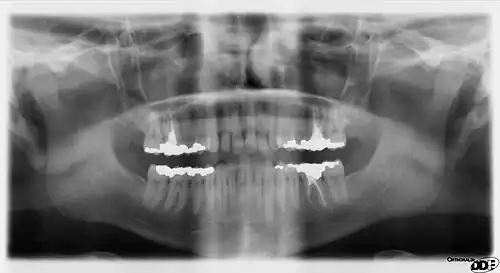

Panoramic radiograph

A dental panoramic radiograph, showing the maxilla and mandible, all the teeth including the "wisdom teeth," the frontal and maxillary sinuses, the nasal cavity and the temporomandibular joint and other near by head and neck anatomy. | |

A panoramic radiograph is a panoramic scanning dental X-ray of the upper and lower jaw. It shows a two-dimensional view of a half-circle from ear to ear. Panoramic radiography is a form of focal plane tomography; thus, images of multiple planes are taken to make up the composite panoramic image, where the maxilla and mandible are in the focal trough and the structures that are superficial and deep to the trough are blurred.

- Orthodontic assessment. pre and post operative